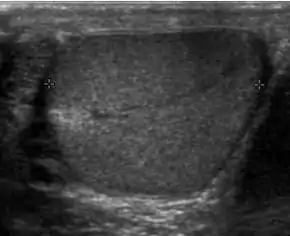

Patients with testicular lymphoma are usually old aged around 60 years of age, present with painless testicular enlargement and less commonly with other systemic symptoms such as weight loss, anorexia, fever and weakness. Bilateral testicle involvements are common and occur in 8.5% to 18% of cases. At sonography, most lymphomas are homogeneous and diffusely replace the testis [Fig. 7]. However focal hypoechoic lesions can occur, hemorrhage and necrosis are rare. At times, the sonographic appearance of lymphoma is indistinguishable from that of the germ cell tumors [Fig. 8], then the patient's age at presentation, symptoms, and medical history, as well as multiplicity and bilaterality of the lesions, are all important factors in making the appropriate diagnosis.

Doppler ultrasound of epididymitis, seen as a substantial increase in blood flow in the left epididymis (top image), while it is normal in the right (bottom image). The thickness of the epididymis (between yellow crosses) is only slightly increased (7 mm).

Doppler ultrasound of the scrotum of the same case, in the axial plane, showing orchitis (as part of epididymo-orchitis) as hypoechogenic and slightly heterogenic left testicular tissue (right in image), with an increased blood flow. There is also swelling of peritesticular tissue.